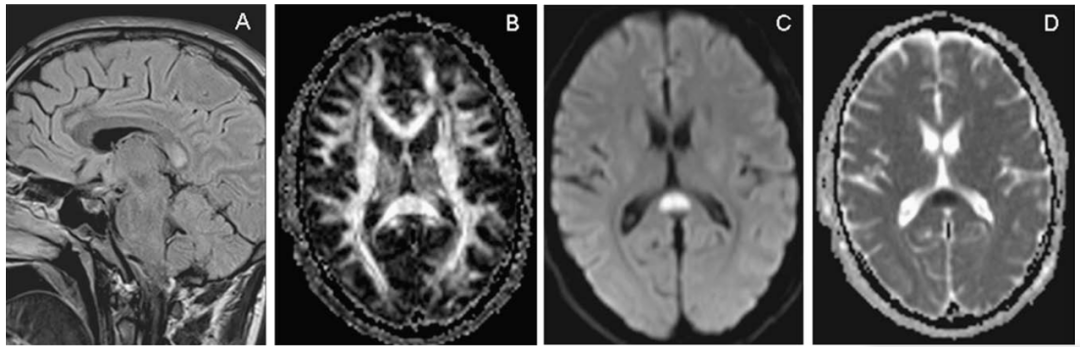

韦尼克脑病

这是由于维生素B1缺乏引起的中枢神经系统代谢性脑病,酗酒是最常见的诱发因素。临床以精神症状、眼肌麻痹和共济失调三主征为主要表现,MRI异常信号围绕第三/第四脑室和导水管。最常受累的结构为乳头体,见于80%的韦尼克脑病患者。如果丘脑背内侧受累,常伴有记忆力障碍。

颅脑MRI冠状位示:双侧乳头体高信号

增强扫描示:双侧乳头体中心强化

颅脑MRI轴位示:双侧乳头体、导水管周围、

穹窿、丘脑背内侧及大脑皮层对称性高信号